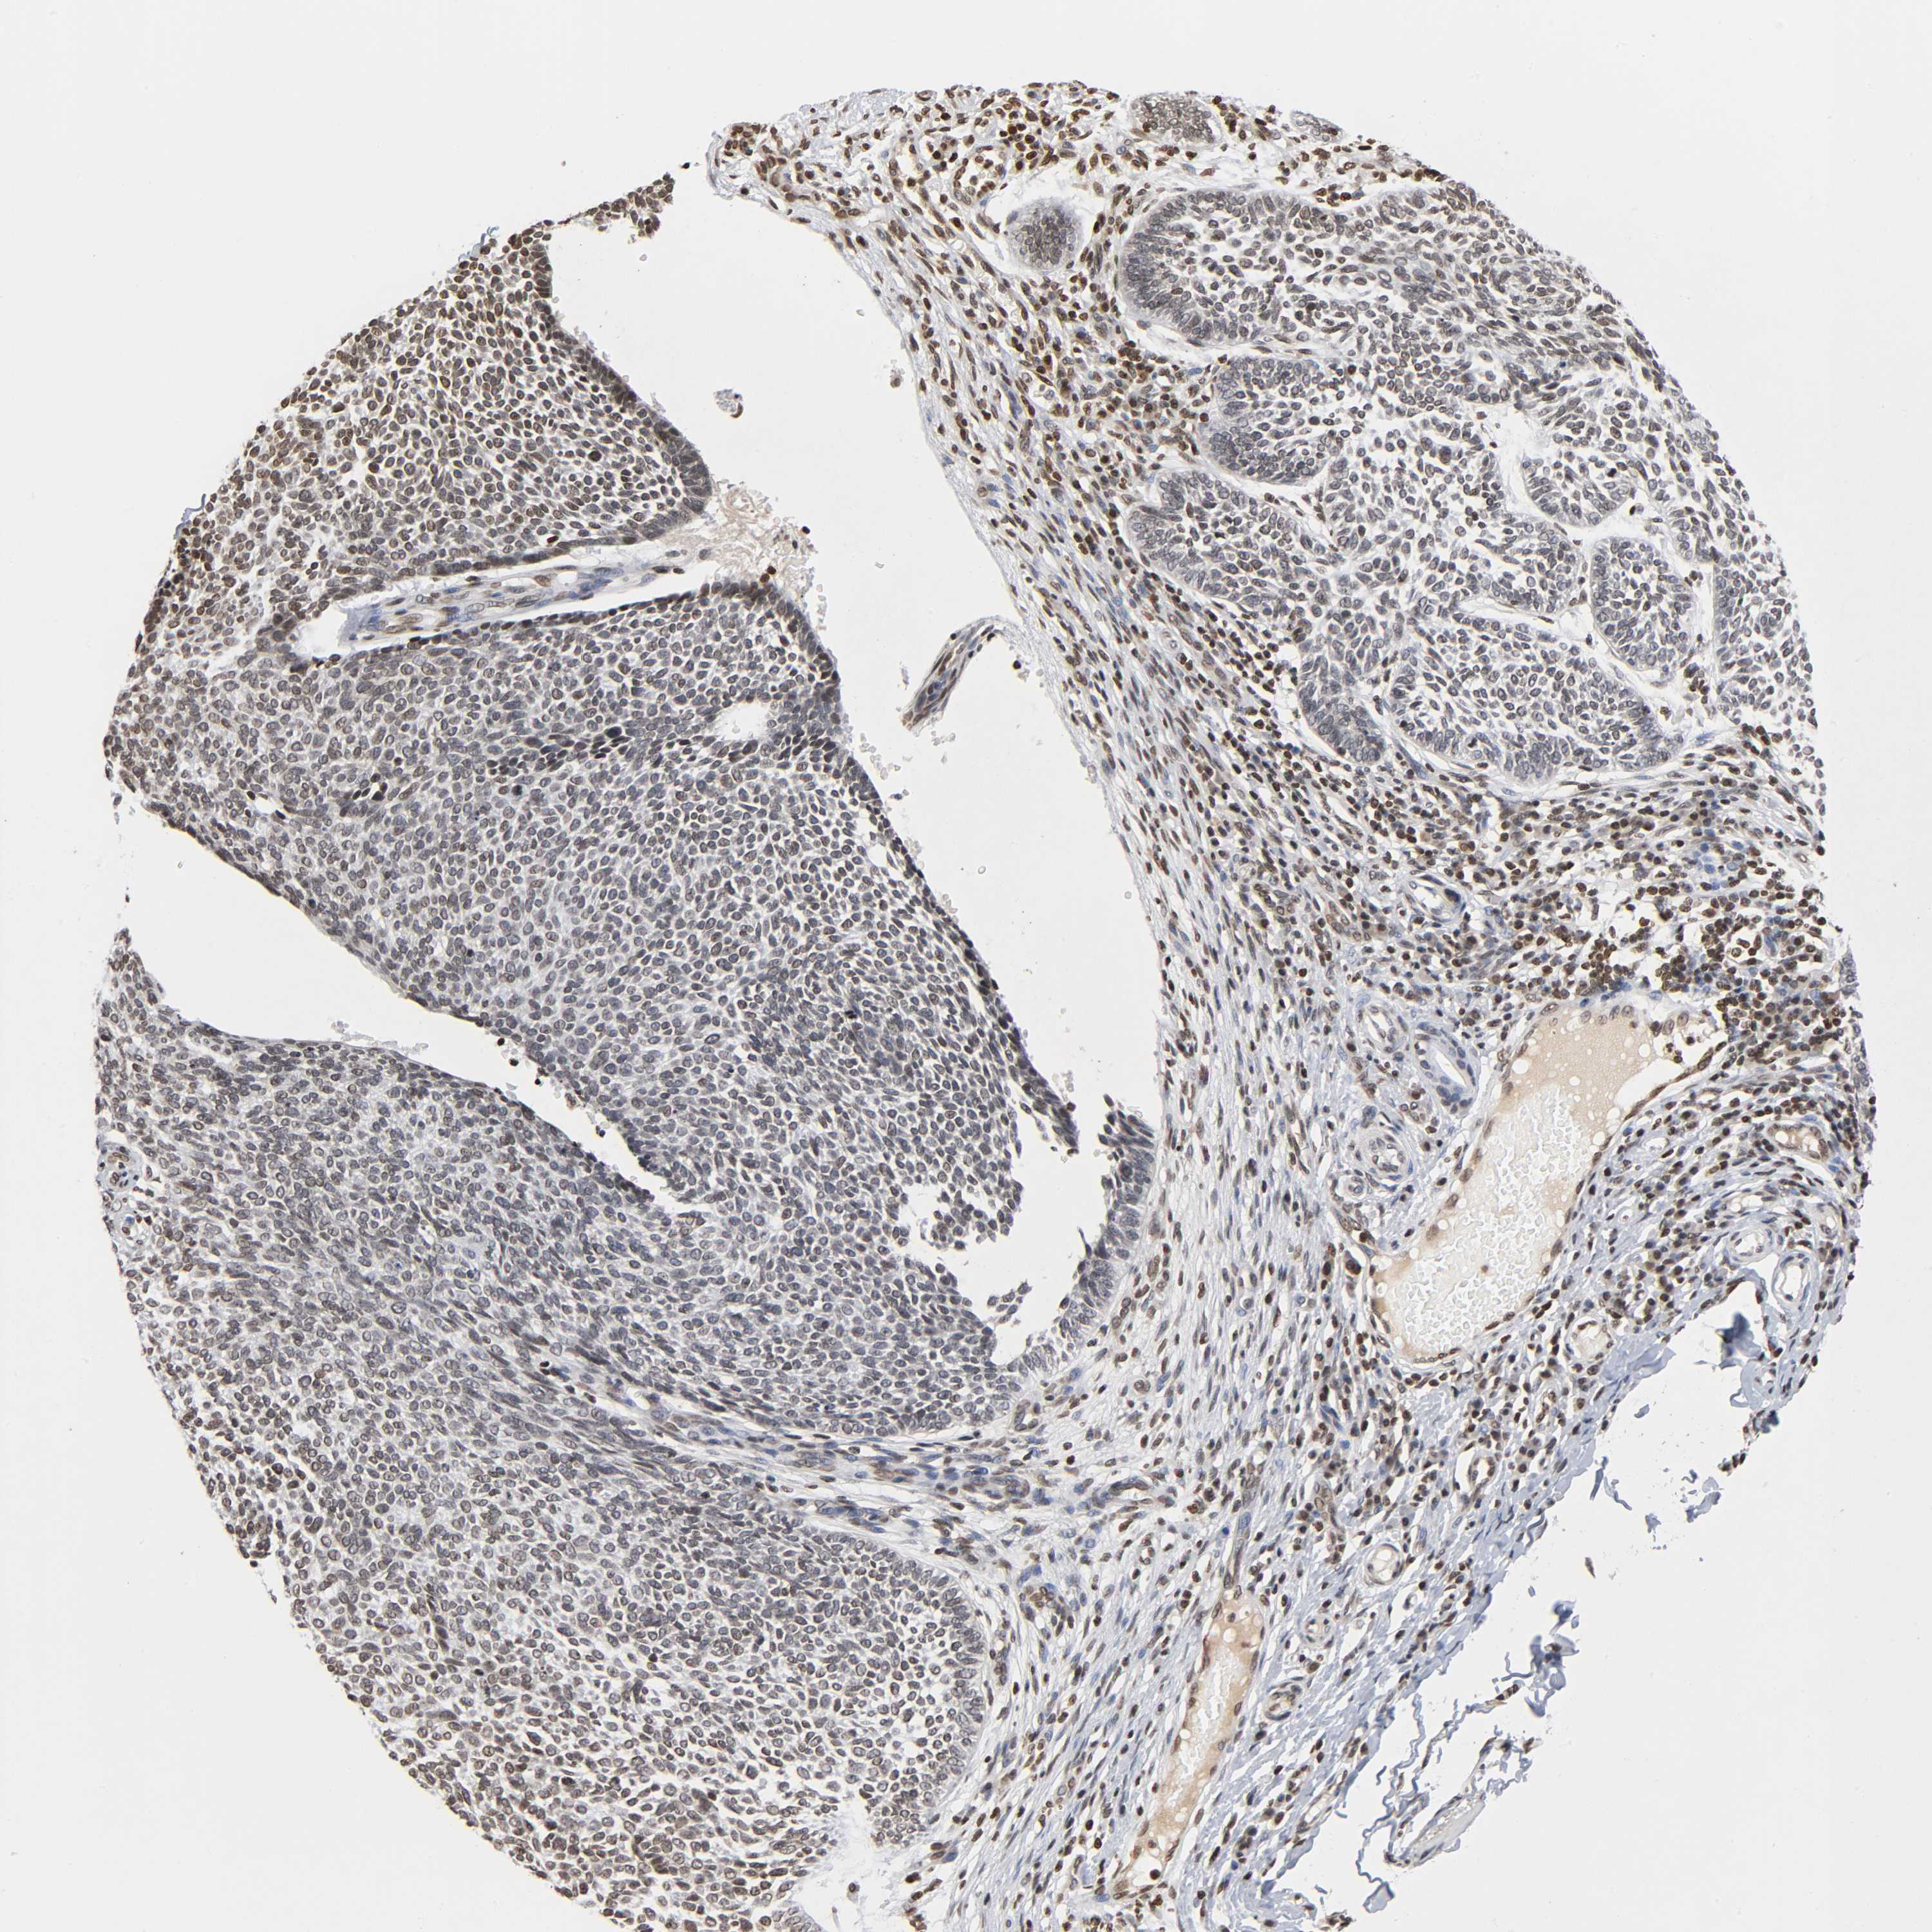

Basal cell and squamous cell cancer

SKIN CANCER - Protein expressioni

A mouse-over function shows sample information and annotation data. Click on an image to view it in a full screen mode. Samples can be filtered based on level of antibody staining by selecting one or several of the following categories: high, medium, low and not detected. The assay and annotation is described here.

Each image is clickable and will lead to virtual microscopy that enables deeper exploration of all samples and also displays staining intensity scores, fraction scores and subcellular localization as well as patient and tissue information for each sample.

Antibody HPA004203

Staining

High

Intensity

Strong

Quantity

>75%

Location

Nuclear

Squamous cell carcinoma, NOS

Basal cell carcinoma